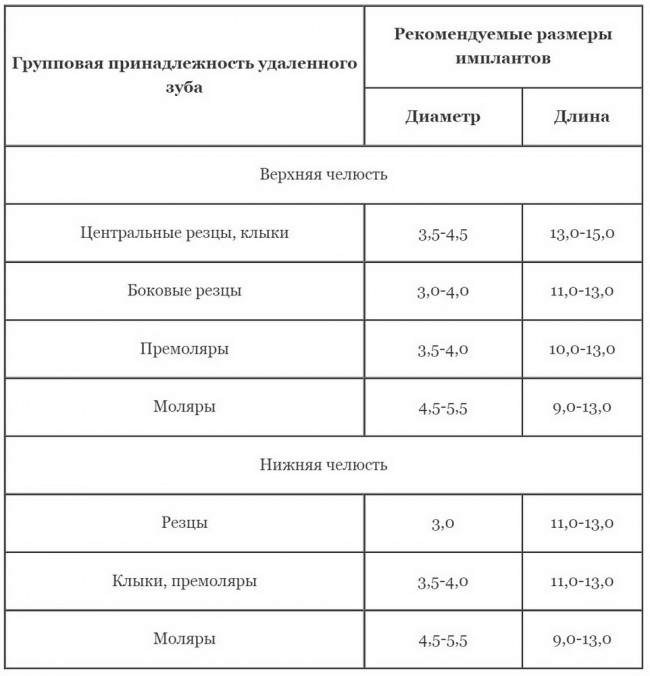

Однако, если рассматривать имплантологическое лечение как воссоздание функционального и эстетического зуба, пусть и искусственного, то приоритеты и подход определенно меняются. Все естественные зубы имеют свои размеры, положение в челюстной кости и определенное соотношение с соседними зубами. И, если мы хотим добиться идеального результата имплантологического лечения, нам необходимо воссоздать этот зуб во всех подробностях: начиная от размера и заканчивая углами наклона и отношением к антагонистам. Так в нашей работе появляется имплантологическое правило #2:

размер и положение импланта в челюстной кости должны максимально соответствовать размеру и положению естественного зуба

любое отступление от этого правила является компромиссом с непредсказуемыми результатом и последствиями, и нести ответственность за такую работу весьма сложно.

(Васильев С., 2013)

Безусловно, эта таблица допускает вариации, но, тем не менее, наглядно отражает зависимость размера имплантов от размера зуба, который планируется к замещению.